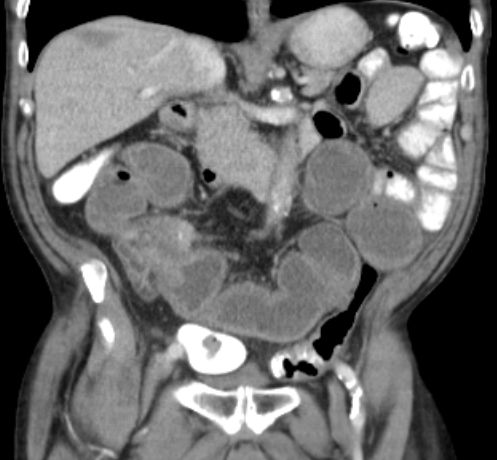

Magen 62-jährige Frau mit kolikartigen Flankenschmerzen durch einen mittlerer Harnleiterstein. Bei der Durchuntersuchung fand sich eine verdickte Magenwand. Endoskopisch chronische, nicht aktive Entzündung mit foveolärer Hyperplasie. Die Biopsie ergab Infiltrate eines gering differenzierten neuroendokrinen Karzinoms (G3, Ki 67 40%). Bekannte Haemangiome der Leber.